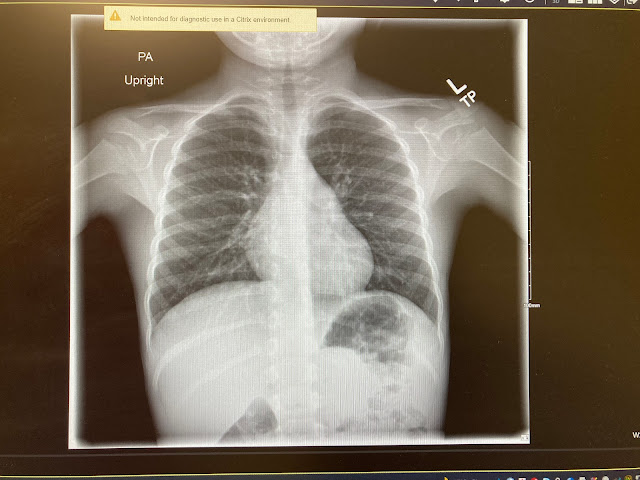

After his lunch, we packed up and headed into the Kapolei urgent care which managed to fit him in between other appointments. They did lots of blood tests, chest x-rays, a urinalysis, and a triple swab for covid, the flu, and another virus.